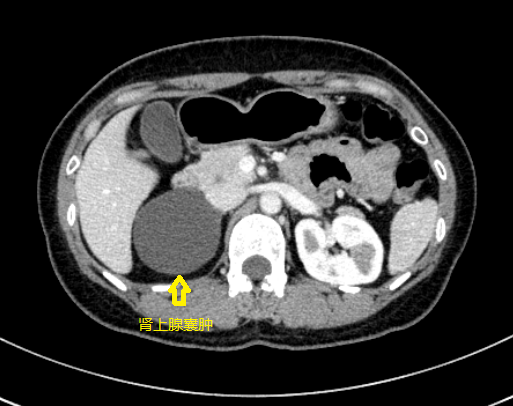

案例一